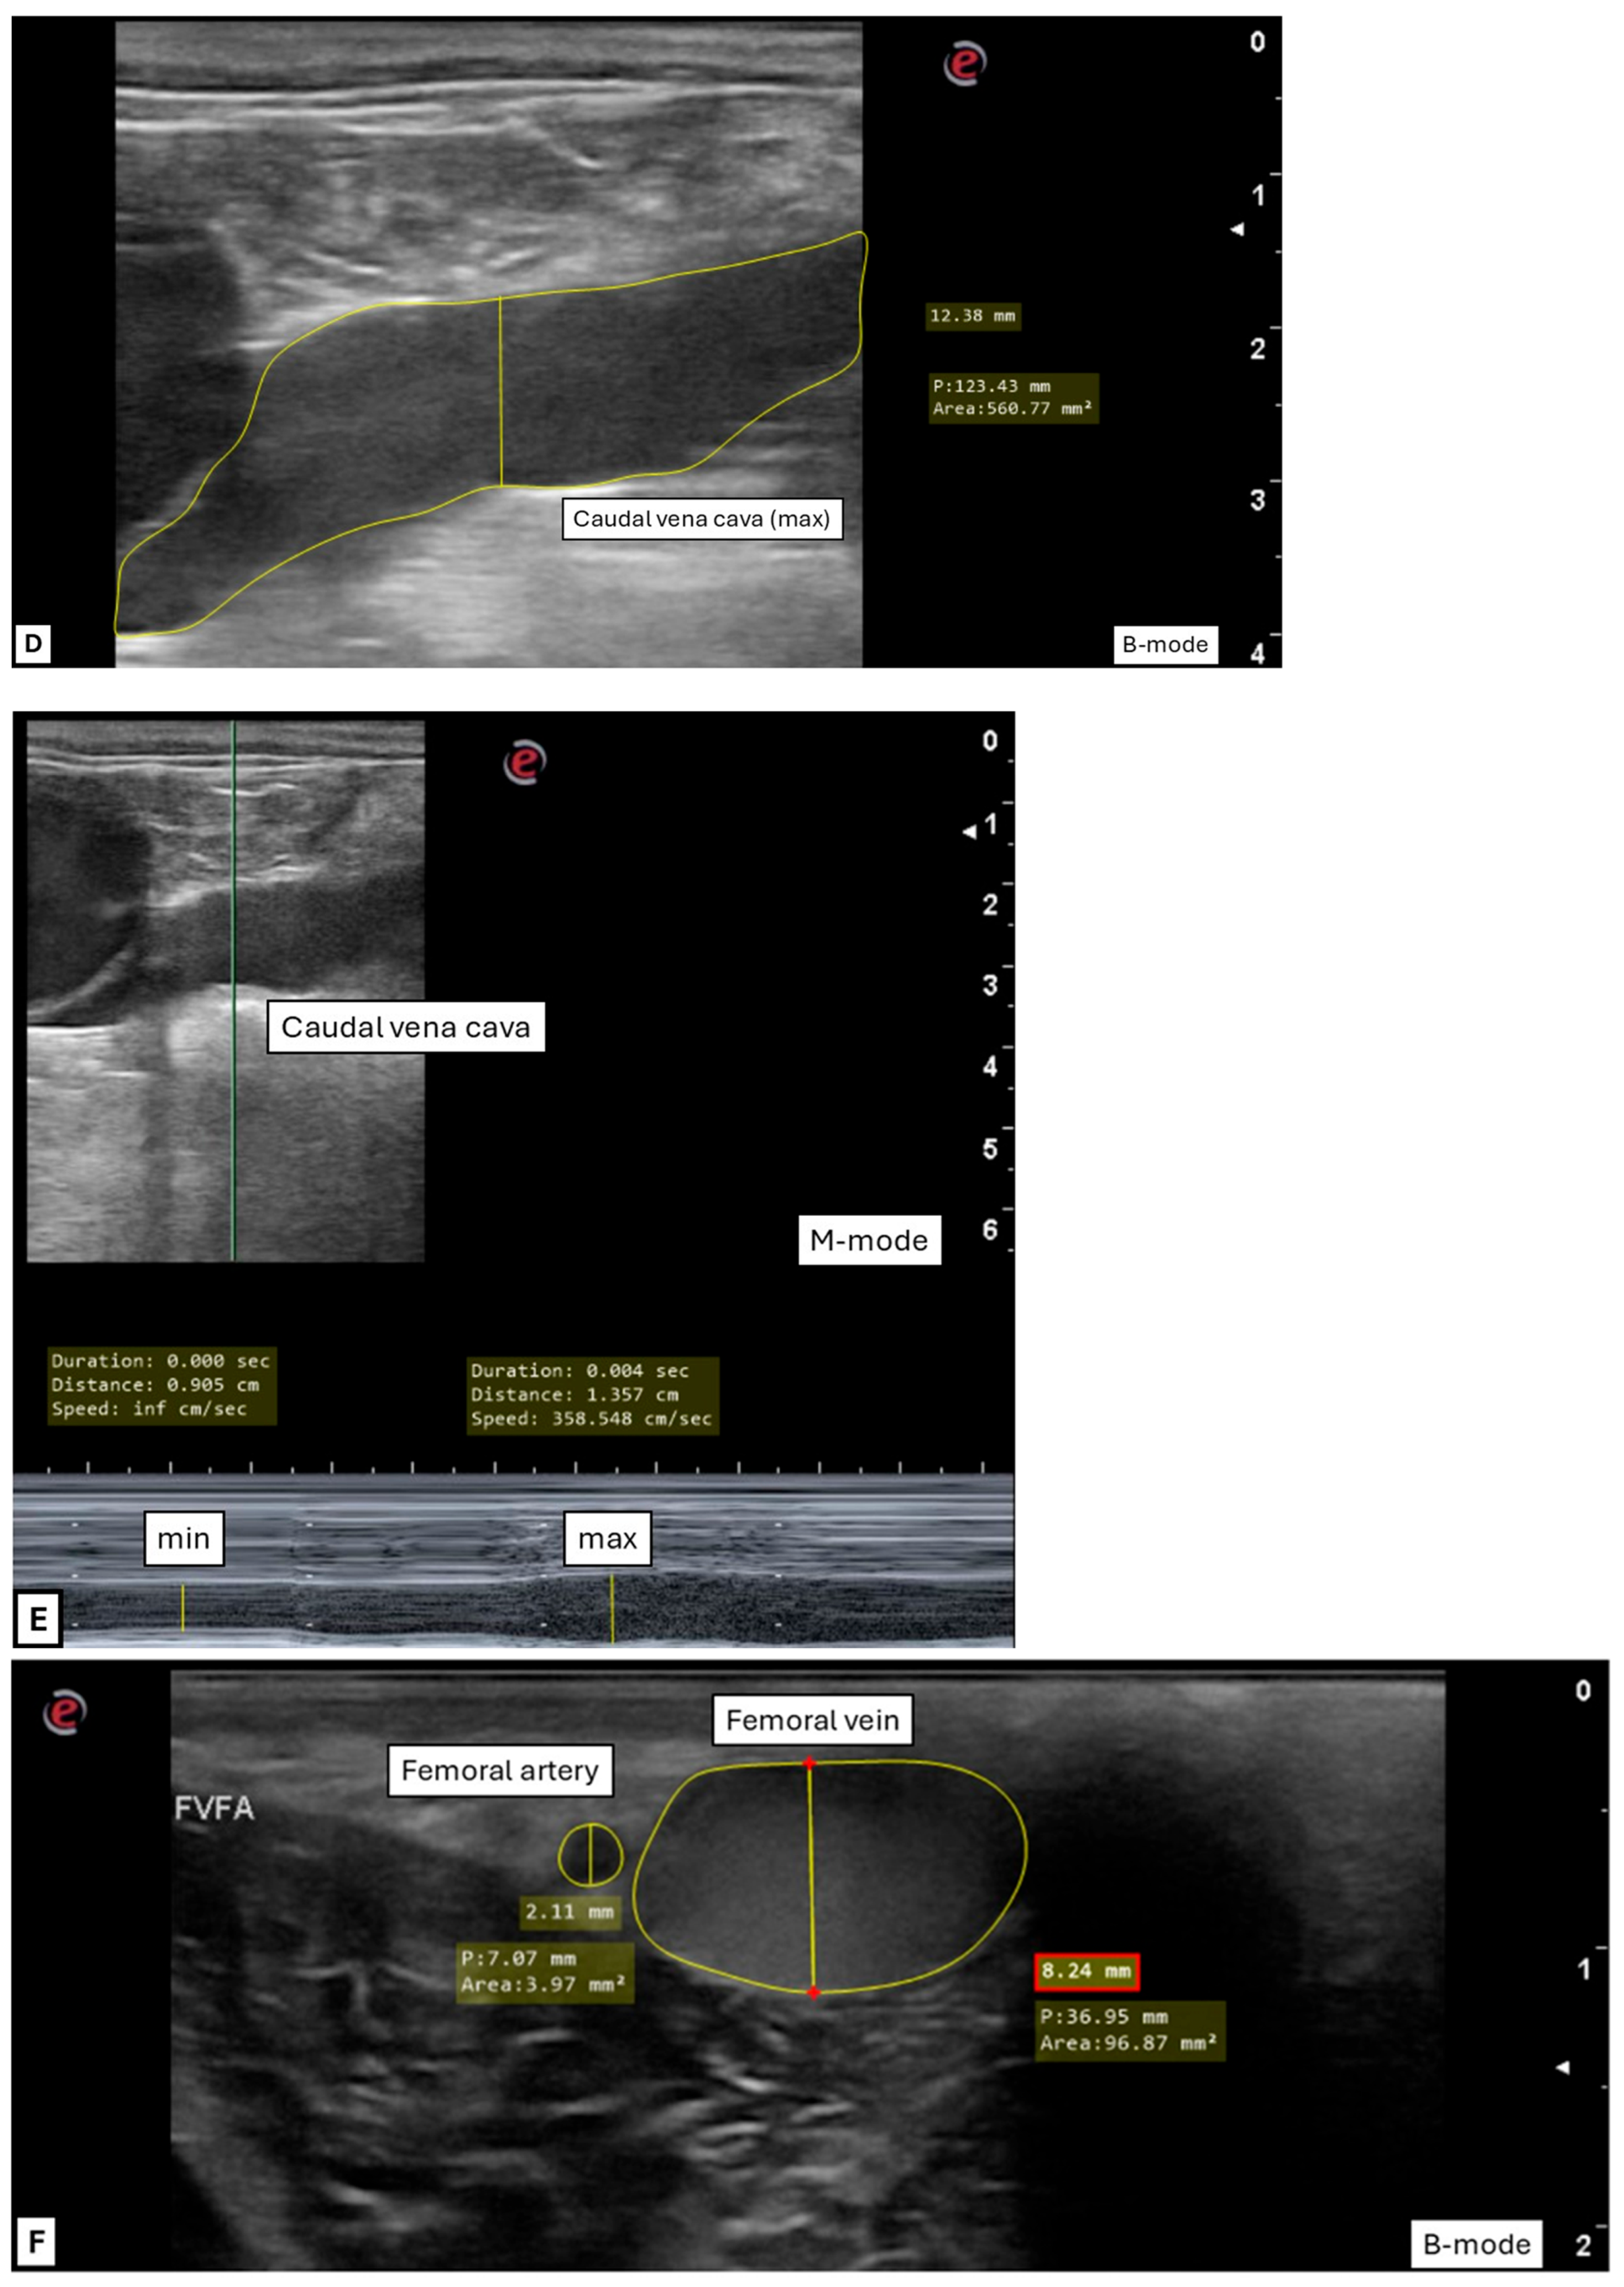

| B-Mode | M-Mode | |||||

|---|---|---|---|---|---|---|

| Mean ± SD | Median (IQR) | 95% CI (Lower-Upper) | Mean ± SD | Median (IQR) | 95% CI (Lower-Upper) | |

| CI CVC on diam | 0.30 ± 0.13 | n/a | (0.27–0.33) | 0.33 ± 0.12 | n/a | (0.30–0.36) |

| CI CVC on area | 0.36 ± 0.15 | n/a | (0.32–0.40) | n/a | n/a | n/a |

| CVC/Ao diam | 0.43 ± 0.15 | n/a | (0.40–0.46) | 0.43 ± 0.11 | n/a | (0.40–0.46) |

| CVC/Ao area * | n/a | 0.56 (0.53–0.64) | n/a | n/a | n/a | n/a |

| Vessel | Median (IQR) |

|---|---|

| FA diam (cm) * | 0.2 (0.22–0.25) |

| FA area (cm2) * | 0.04 (0.04–0.05) |

| FV diam (cm) * | 0.8 (0.82–0.97) |

| FV area (cm2) * | 1.0 (1.08–1.46) |

| Mean ± SD | Median (IQR) | 95% CI (Lower-Upper) | |

|---|---|---|---|

| FV/FA diam | 3.80 ± 1.02 | n/a | (3.54–4.05) |

| FV/FA area * | n/a | 26.74 (25.23–32.40) | n/a |